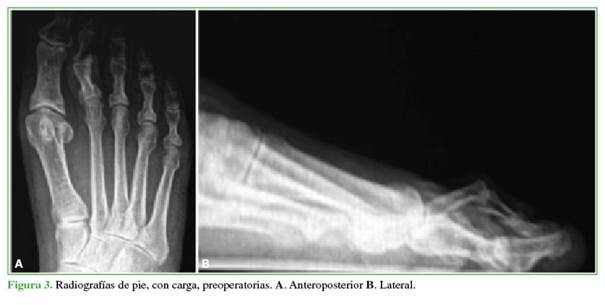

Los pacientes fueron evaluados clínica y radiológicamente antes de la cirugía, a las 3 semanas, a los 3 meses, o hasta constatar la consolidación (Figuras 3 y 4).